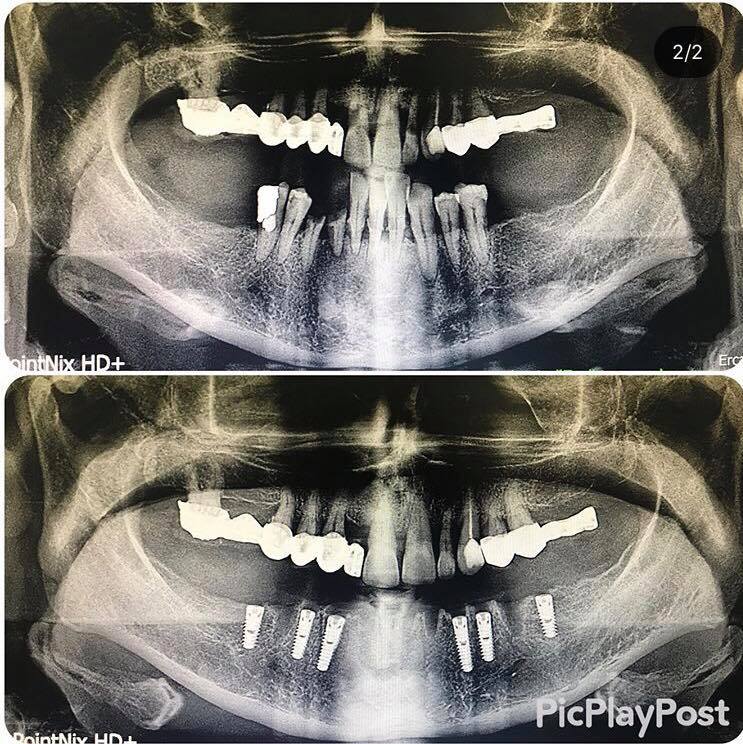

implant tedavisi